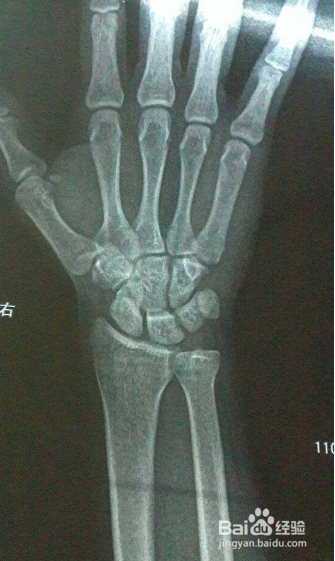

1、去除身体的金属物体

患者在CT检查时需要去除身体的金属部位,只有去除金属物体,才能避免在检查过程中金属物体上的辐射造成的伪影,这很容易导致误差的结果。